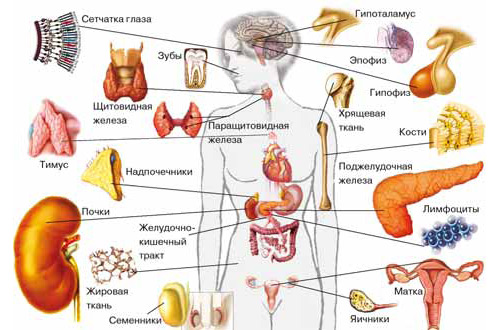

РИКАС программа по иммунологии (13 параметров из 55 на выбор, 2 раза в месяц)

Программа внешней оценки качества по иммунологии - RIQAS Immunoassay programme (13 параметров из 55 на выбор, 2 раза в месяц).

РИКАС программа по иммунологии (55 параметров, 1 раз в месяц)

Программа внешней оценки качества по иммунологии - RIQAS Monthly immunoassay programme (55 параметров, 1 раз в месяц).

РИКАС программа по иммунологии (55 параметров, 2 раза в месяц)

Программа внешней оценки качества по иммунологии - RIQAS Immunoassay programme (55 параметров, 2 раза в месяц).

РИКАС программа по иммунологии (4 параметра из 55 на выбор, 2 раза в месяц)

Программа внешней оценки качества по иммунологии - RIQAS Immunoassay programme (4 параметра из 55 на выбор, 2 раза в месяц).

РИКАС программа скрининга беременности (6 параметров, 1 раз в месяц)

Программа внешней оценки качества скрининга беременности - RIQAS Maternal screening programme (6 параметров, 1 раз в месяц).

РИКАС программа специальная иммунология 1 (10 параметров, 1 раз в месяц)

Контрольные материалы для проведения внешней оценки качества лабораторных исследований по следующим параметрам: I-25-(ОН)2-витамин D, 25-ОН-витамин D, С-пептид, Анти-ТГ, Анти-ТПО, ИФР-1, Остеокальцин, Прокальцитонин, ПТГ, Инсулин.

РИКАС программа специальная иммунология 2 (5 параметров, 1 раз в месяц)

Программа внешней оценки Специальная иммунология 2 - RIQAS Immumoassay speciality 2 programme (5 параметров, 1 раз в месяц).